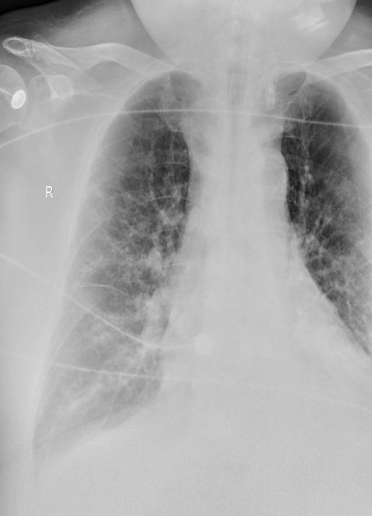

分别在2021年6月10日11日13日进行了SBT,结果均失败。在同样模式参数情况下,患者晨起PaCO2增高。与入科时相比,患者右肺透亮度有所增加(图8),膈肌活动度为1.92,厚度为0.06(图9)。WBC略微增高,但仍在可控范围,PCT 0.01 ng/ml,血清G试验测值197.56,血清GM试验测值0.179。血气分析示患者PaO2升高,氧合指数增加(图10)。其他综合评估见表4

图片

图8  第一阶段治疗后患者胸部X线片